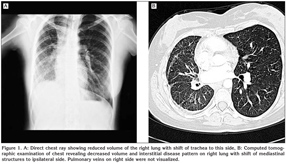

A 20-year-old female college student admitted to our clinic with dsypnea on exertion. She had this complaint for two years. On her past medical history she had pneumonia three years ago. On physical examination respiratory sounds were decreased on right hemithorax and cracles were heard on base of the right lung. Direct chest X-ray was obtained which revealed reduced volume of the right lung with shift of trachea to this side (Figure 1A). Computed tomographic examination of the chest showed decreased volume and interstitial disease pattern on right lung with shift of mediastinal structures to ipsilateral side. Right pulmonary veins were not identified on tomographic scans (Figure 1B). On transthoracic Doppler echocardiographic examination the right pulmonary veins were also could not be visualized. The estimated systolic pulmonary pressure on Doppler examination was normal. The right and left ventricular function were found as normal and interatrial and interventricular septums were intact. To confirm the diagnosis cardiac catheterization and pulmonary angiography were performed. On oxymetric study oxygen saturation was higher on right pulmonary artery than that of the left (99% vs. 89%, respectively). This finding suggested the presence of systemic arterial blood flow to pulmonary arteries on the affected side. On selected left pulmonary artery angiography the perfusion of the left lung was identified to be normal with normal pulmonary veins draining into left atrium (Figure 2A). However on selected right pulmonary angiography decreased perfusion of the right lung was noted and pulmonary veins on this side were not visualized (Figure 2B). Instead prominent intercostal arteries were identified supplying blood to the right lung. The patient was discussed with cardiologists and cardiovascular surgeons and conservative approach was chosen for her. She and her family were informed about this condition and close follow up were scheduled.

Figure 2